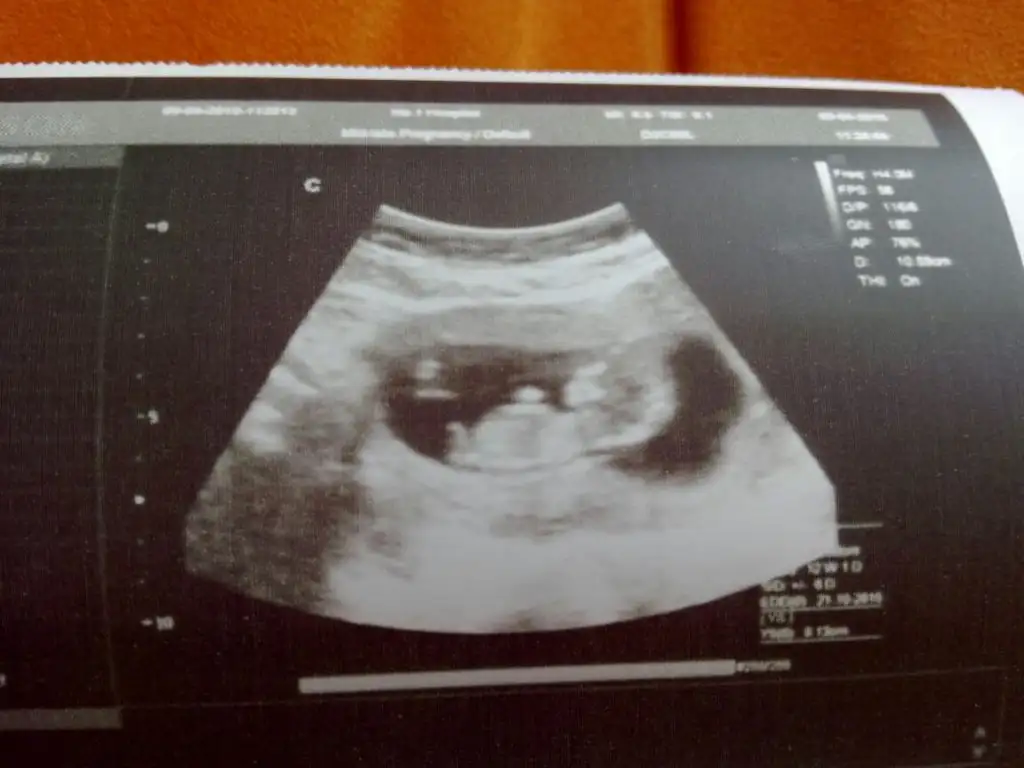

Erkek bence bu bebisBana da yorum yapabilir misin 11 haftalik burda ama çok merak ediyorum

Erkeğe benzettim canım :)Bana da yorum yapabilir misin 11 haftalik burda ama çok merak ediyorum

Erken zaten canım büyüsün netleşir inşAllah :):) ama yüksek ihtimal erkek gibi :)

Erkek bence bu bebis